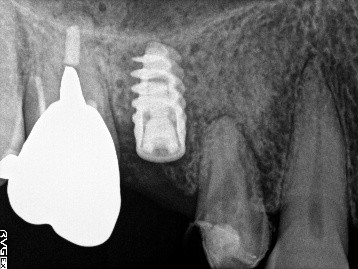

歯根が破折していましたので、抜歯しました。抜歯後インプラント治療を希望されました。歯根が破折していた状態で1年以上経過していましたので、大きく骨が欠損していました。骨造成をして、6か月待ってからCT撮影をし、骨ができていることを確認してからインプラントを埋入しました。

Before

抜歯をし骨造成後5か月経過

After

2022年2月のインプラント治療